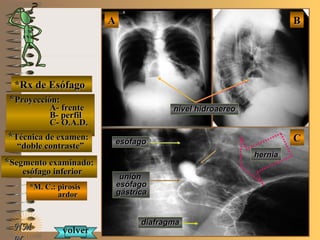

*Rx de Esófago*Rx de Esófago

**Proyección:Proyección:

A-A-

B-B-

C-C-

**Técnica de examen:Técnica de examen:

**Segmento examinado:Segmento examinado:

*M. C.: pirosis*M. C.: pirosis

ardorardor

NMNM

BBAA

CC

frentefrente

perfilperfil

O.A.D.O.A.D.

““doble contraste”doble contraste”

esófago inferioresófago inferior

A-A-El examen es normal o patológico?El examen es normal o patológico?

Examen patológico de esófago inferior con téc-Examen patológico de esófago inferior con téc-

nica de doble contraste en proyección O.A.D. ynica de doble contraste en proyección O.A.D. y

telerradiografía de tórax (frente y perfil)telerradiografía de tórax (frente y perfil)

B-B-La patología es congénita o adquirida?La patología es congénita o adquirida?

Patología adquiridaPatología adquirida

C-C- Dicha patología es orgánica, funcional o mixta?Dicha patología es orgánica, funcional o mixta?

**OpciónOpción

de volverde volver

a ver lasa ver las

imágenesimágenes

Patología adquirida orgánicaPatología adquirida orgánica

D-D-La misma es neoplásica o no neoplásica?La misma es neoplásica o no neoplásica?

Patología adquirida orgánica no neoplásicaPatología adquirida orgánica no neoplásica

E-E-Puede describir la o las imágenes patológicas?Puede describir la o las imágenes patológicas?

Se evidencia en el tórax un nivel hidroaereo re-Se evidencia en el tórax un nivel hidroaereo re-

trocardíaco, que en el examen contrastado detrocardíaco, que en el examen contrastado de

esófago se corrobora como una hernia hiatalesófago se corrobora como una hernia hiatal

parcialmente reductible y con reflujo gastro-parcialmente reductible y con reflujo gastro-

esofágicoesofágico

**Opción avanzada para volver a ver las imágenes con reparosOpción avanzada para volver a ver las imágenes con reparosNMNM